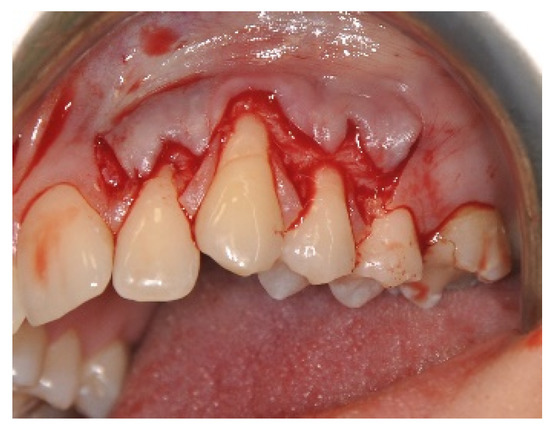

2.3. Surgical Procedures